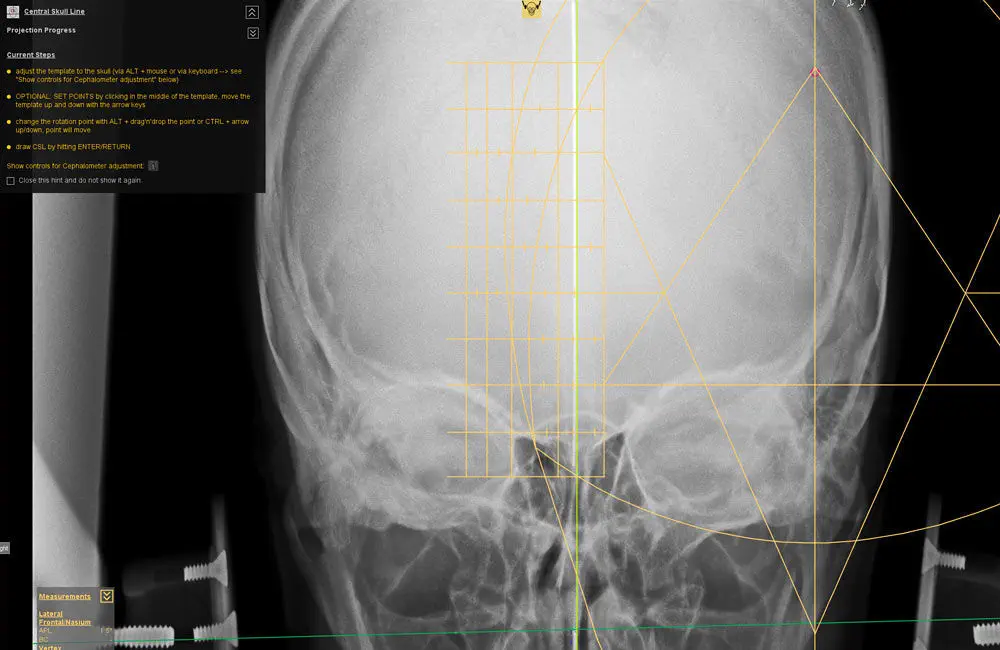

X線写真臨床検査の カイロプラクティック用 参考図書 スカイ

X線写真臨床検査の カイロプラクティック用 参考図書 スカイ

X線写真臨床検査の カイロプラクティック用 参考図書 スカイ,

X線写真臨床検査の カイロプラクティック用 参考図書 スカイ, X線写真臨床検査の カイロプラクティック用 参考図書 スカイ,

X線写真臨床検査の カイロプラクティック用 参考図書 スカイ, Amazon.co.jp: TK26-018 スカイイースト X線写真臨床検査の,

Amazon.co.jp: TK26-018 スカイイースト X線写真臨床検査の, X線検査装置(CT) : 分析計測機器(分析装置) 島津製作所,

xe-zenshini-h-2060-1.jpg, 診断用ソフト - dicomPACS® - OR Technology - Oehm und Rehbein,

診断用ソフト - dicomPACS® - OR Technology - Oehm und Rehbein, カイロプラクティック検査法| 姿勢分析